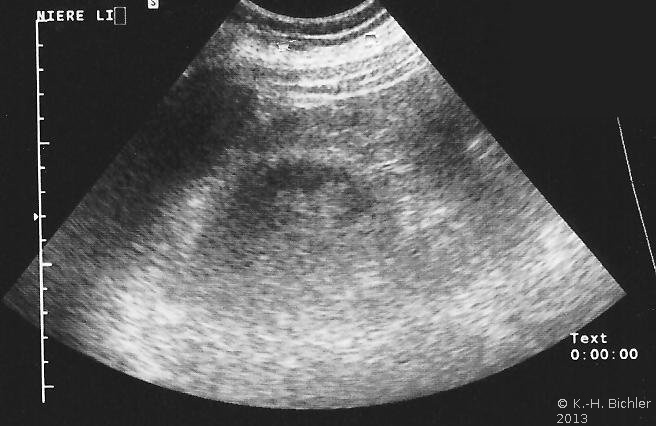

In der Sonographie fand sich eine kleine Niere links bei unauffälliger rechter Niere (Abbildung 18b).

Das Mädchen kam wegen Fieber (39°C), Flankenschmerzen und Blutdruckwerten um 140 zu 80 mmHg in urologische Behandlung. Die eingeleiteten Untersuchungen ergaben sonographisch eine leicht verkleinerte linke Niere, im Labor ein unauffälliges Urinbild, mikrobiologisch negativ, im Serum unauffällige Entzündungsparameter.